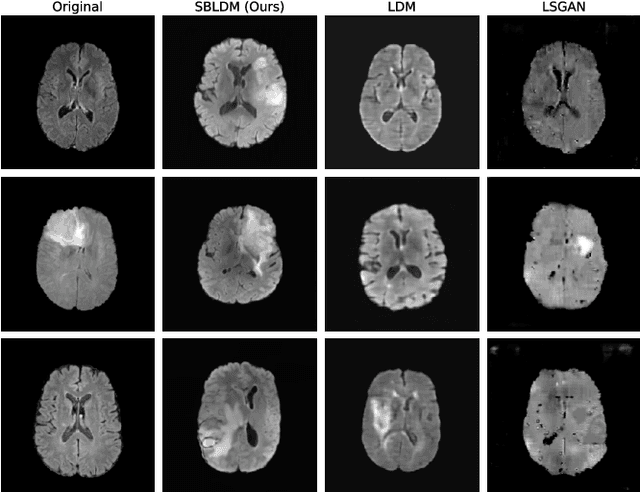

Abstract:Despite the increasing use of deep learning in medical image segmentation, the limited availability of annotated training data remains a major challenge due to the time-consuming data acquisition and privacy regulations. In the context of segmentation tasks, providing both medical images and their corresponding target masks is essential. However, conventional data augmentation approaches mainly focus on image synthesis. In this study, we propose a novel slice-based latent diffusion architecture designed to address the complexities of volumetric data generation in a slice-by-slice fashion. This approach extends the joint distribution modeling of medical images and their associated masks, allowing a simultaneous generation of both under data-scarce regimes. Our approach mitigates the computational complexity and memory expensiveness typically associated with diffusion models. Furthermore, our architecture can be conditioned by tumor characteristics, including size, shape, and relative position, thereby providing a diverse range of tumor variations. Experiments on a segmentation task using the BRATS2022 confirm the effectiveness of the synthesized volumes and masks for data augmentation.

Abstract:Despite the increasing use of deep learning in medical image segmentation, acquiring sufficient training data remains a challenge in the medical field. In response, data augmentation techniques have been proposed; however, the generation of diverse and realistic medical images and their corresponding masks remains a difficult task, especially when working with insufficient training sets. To address these limitations, we present an end-to-end architecture based on the Hamiltonian Variational Autoencoder (HVAE). This approach yields an improved posterior distribution approximation compared to traditional Variational Autoencoders (VAE), resulting in higher image generation quality. Our method outperforms generative adversarial architectures under data-scarce conditions, showcasing enhancements in image quality and precise tumor mask synthesis. We conduct experiments on two publicly available datasets, MICCAI's Brain Tumor Segmentation Challenge (BRATS), and Head and Neck Tumor Segmentation Challenge (HECKTOR), demonstrating the effectiveness of our method on different medical imaging modalities.